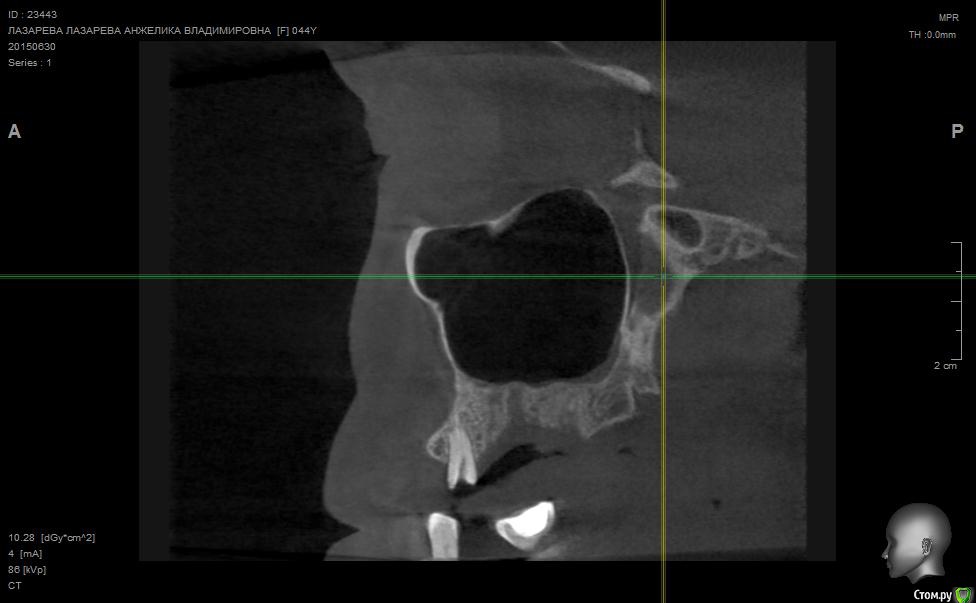

Angelika Опубликовано 2 июля, 2015 Поделиться Опубликовано 2 июля, 2015 Добрый день!Помогите,пожалуйста!!!!!!8 мая имплантолог(!) удалил 2 зуба-27(резерцин-формалиновый) и 28 (нелеченный).Удаление было очень долгим и травматичным,почуяв неладное,хотела убежать прямо из кресла.Последствия-одонтогенный гайморит,не считая незаживающих лунок .В начале июня отлежела в ЧЛХ(антибиотики,физио).26 июня сделала КТ.Нос пришел в норму более-менее,а вот челюсть....((((( Из заключения: 26,27,зубы отсутствуют. В альвеолярном отростке верхней челюсти в области отсутствующего 26 и 27 зуба визуализируется дефект костной ткани размерами до 9,6*14,0*7,2 мм с неровными и нечеткими контурами, с множественными мелкими и крупными секвестрами, с разрушеннымиоральной кортикальной пластинкой альвеолярного отростка верхней челюсти на протяжении до 12,9мм, и вестибулярной замыкательной пластинкой на протяжении до 19,1 мм. Рентгенологическихпризнаков свидетельствующих о наличии свищевого хода, ороантрального соустья - не выявлено,целостность нижней стенки левой верхнечелюстной пазухи полностью восстановлена на всем протяжении. Положительная динамика от 26.05.15г. В альвеолярном отростке, в области корней отсутствующего 28 зуба, определяются нечеткиеконтуры лунки удаленного зуба и единичный фрагмент корня размерами до 1,9*1,7*2,7 мм. В областиотсутствующего 28 зуба и бугра верхней челюсти слева визуализируются единичные мелкие участки остеопороза костной ткани альвеолярного отростка верхней челюсти, в следствие исхода воспалительного процесса. Посоветуйте,пожалуйста,нужно ли удалять обломок корня 28 зуба,если он такой маленький,а лунка уже затянулась.Что мне делать,как это залечить,болит вся челюсть с левой стороны.(((((( О имплантах и забыла уже,восстановиться бы после такой травмы.....Помогите!!! Что делать,как залечить все это?Снимки прилагаю. Ссылка на комментарий

Alejandro Опубликовано 2 июля, 2015 Поделиться Опубликовано 2 июля, 2015 На бумаге страшнее, чем на снимке. Лучший врач для Вас теперь - время. Со временем, кстати, станет понятно: что делать с остатком корня, экстренности пока никакой нет. Успокойтесь, сложные удаления довольно часто встречаются. Очень хорошо, что нет ороантрального сообщения. 2 Ссылка на комментарий

Bier Опубликовано 5 июля, 2015 Поделиться Опубликовано 5 июля, 2015 нет. У Вас на рентгене картина свежего удаления. Т.е. в рамках нормы 2 Ссылка на комментарий

Bier Опубликовано 7 июля, 2015 Поделиться Опубликовано 7 июля, 2015 думаю, что проблем там нет. На снимке все не так плохо, как в описании. Все хорошо будет. Ссылка на комментарий